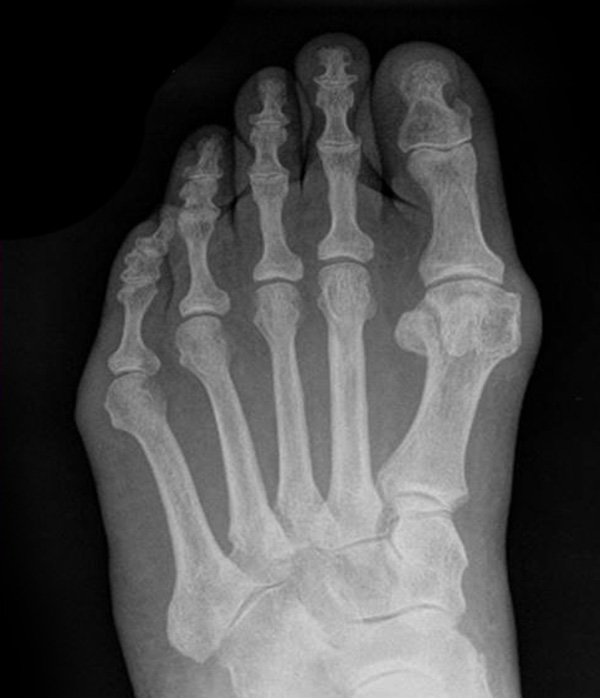

Abb. 7 a, b: Typ II Deformität mit prä- (a) und postoperativem Röntgenbild (b) mit K-Draht Osteosynthese und gleichzeitiger Hallux valgus Korrektur.

Abb. 8 a, b, c: Typ III Deformität mit prä- (a) und postoperativem Röntgenbild (b, c) mit Schrauben-Osteosynthese.

Abb. 9 a, b: Typ III Deformität mit prä- (a) und postoperativem Röntgenbild (b).